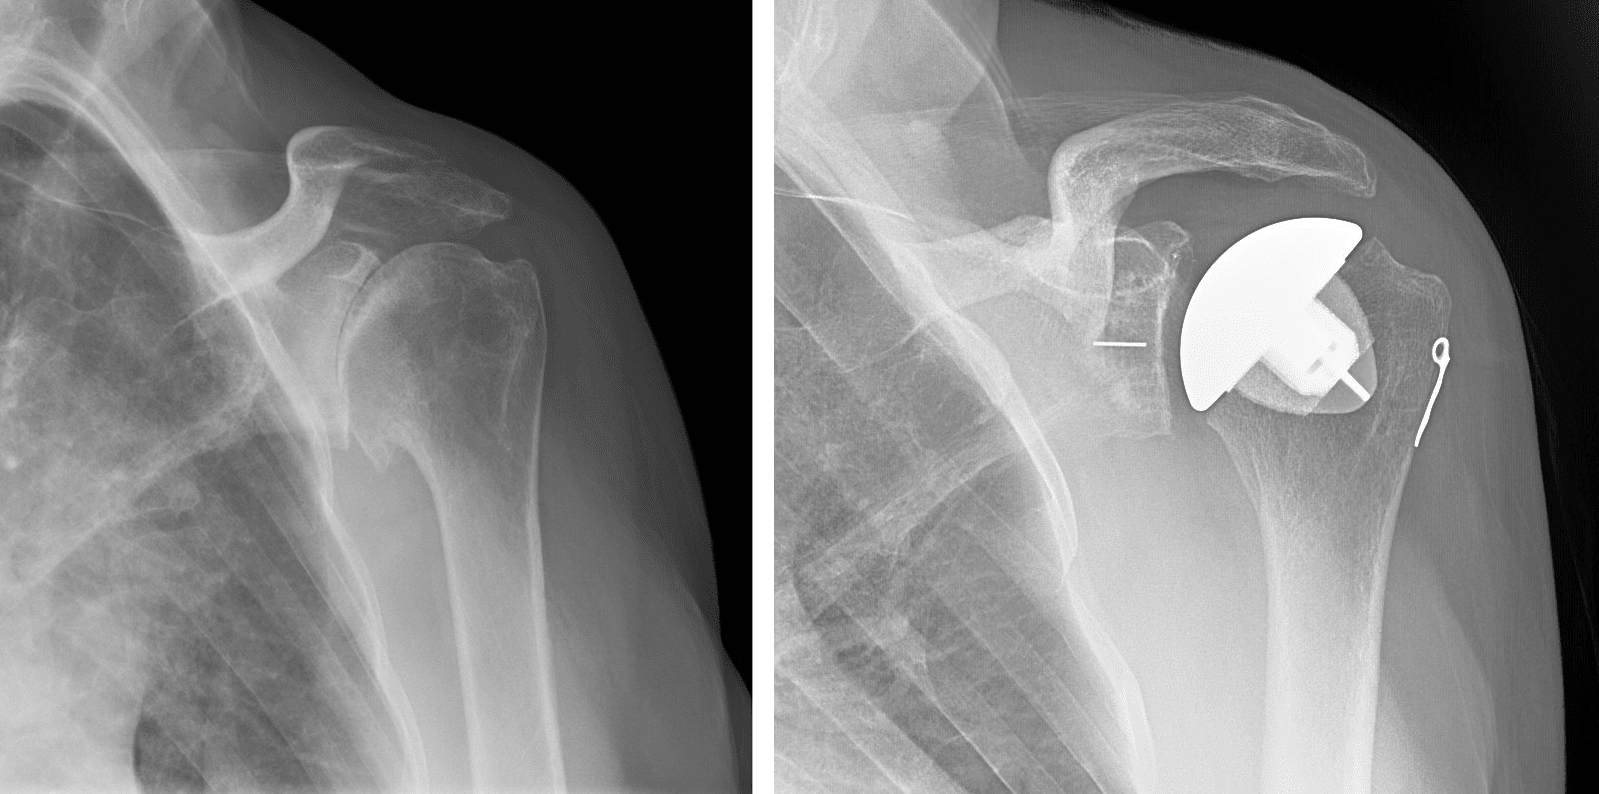

Shoulder Replacement X-Ray . Shoulder replacement removes damaged areas of bone and replaces them with parts made of metal and plastic (implants). If there is an irreparable rotator cuff. Shoulder arthroplasties are a common procedure, being third in joint replacements after knees and hips, and are used to treat a number of. This allows the patient to use the deltoid muscle instead of the torn rotator cuff to lift the arm. Patient suitability for an anatomic shoulder arthroplasty. A standard total shoulder arthroplasty, also known as anatomic total shoulder arthroplasty or total shoulder replacement, aims to replace both the.

Dislocated reverse total shoulder arthroplasty Image Shoulder Replacement X-Ray Shoulder arthroplasties are a common procedure, being third in joint replacements after knees and hips, and are used to treat a number of. This allows the patient to use the deltoid muscle instead of the torn rotator cuff to lift the arm. If there is an irreparable rotator cuff. A standard total shoulder arthroplasty, also known as anatomic total shoulder. Shoulder Replacement X-Ray.

How to read Xray after the TSA (total shoulder arthroplasty) Sumer's Radiology Blog Shoulder Replacement X-Ray If there is an irreparable rotator cuff. Patient suitability for an anatomic shoulder arthroplasty. A standard total shoulder arthroplasty, also known as anatomic total shoulder arthroplasty or total shoulder replacement, aims to replace both the. Shoulder arthroplasties are a common procedure, being third in joint replacements after knees and hips, and are used to treat a number of. Shoulder replacement. Shoulder Replacement X-Ray.